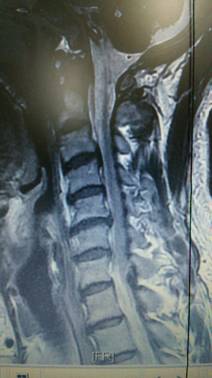

頚椎ヘルニアを専門に治療する整骨院です。交通事故むち打ち治療

手術を考慮された患者さんです。

そもそも医者と患者では、手術に対する意識に大きなギャップがある。その「埋められない溝」について

「患者さんは手術成功と聞くと、『今ある苦しみから解放される』と期待します。一方で、医者としては『このまま放っておくと、亡くなってしまうが、手術することによって寿命が延びる可能性が高まる』という視点。患者側は劇的な改善を求めるのに対し、医者側は命を助けることを最優先にしている。

医学論文の一般的な定義でいうと、『オペ後30日以内』に死亡したかどうかが指標になる。つまり30日生きていれば、患者の回復レベルがどうであれ、手術は『成功』としてカウントされるのです」